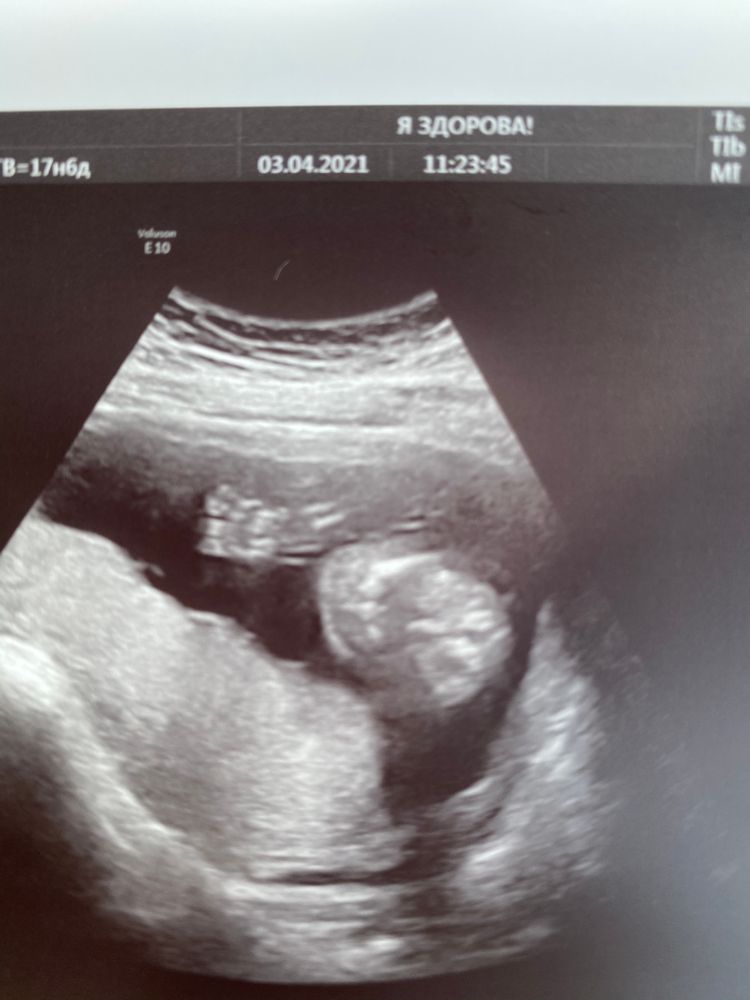

Экспертное узи 16+3💙

УЗИ, КТГ, доплерВчера были на экспертном узи, все показатели отличные и соответствуют срокам, твп в норме и носик тоже, врач успокоила. Наш малыш первым делом сразу всем сообщил, что он гражданин, а не гражданка 😃 помахал ручкой, растрогал папку (тёр глаза, но теперь отрицает 🙈)